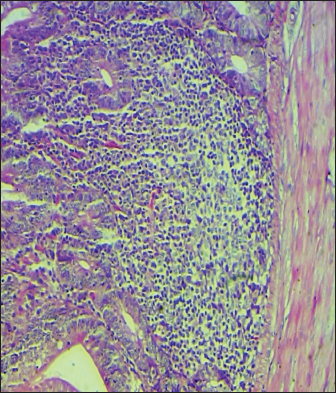

Histopathological study

The results noted in Figures 15 showed that chicks infected with S. enteritidis had edema among the muscular layer with atrophy of some intestinal villi. On the other hand, broilers infected with S. enteritidis and treated with C. myxa showed degeneration of intestinal glands with extensive inflammatory cell infiltration also mild sub-muscular edema, while with curcumin-treated group showed normal intestinal villi architectures, with hyperplasia of intestinal associated lymphoid tissue. The result noted a clear improvement in broilers that received C. myxa and curcumin showing normal intestinal villi with an increase in the number of goblet cells. The data of the present study confirmed the effectiveness of C. myxa and curcumin and especially the synergistic action between them in inhibiting the growth of S. enteritidis bacteria in poultry chickens, improving antioxidants and reducing free radicals, in addition to its action as a good anti-inflammatory at the blood level and suppressing the levels of cytokines that encourage inflammation and its role in improving intestinal tissues and making them close or similar to the health of broiler.

Fig. 4. Cross section of the intestine of poultry infected with S. enteritidis and treated with curcumin showing normal intestinal villi architectures, with hyperplasia of intestinal associated lymphoid tissue (200×, H & E).